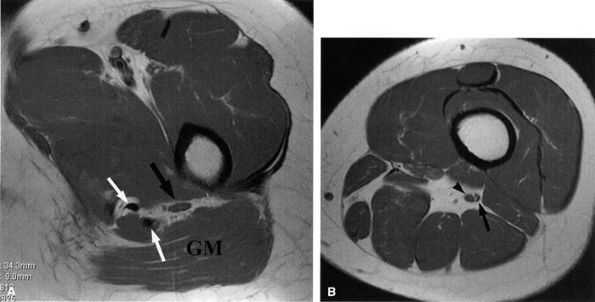

FIGURE 6.10 ● Sciatic neuropathy associated with rhabdomyolysis. Increased signal in the sciatic nerve (arrows) is shown on this coronal fluid-sensitive fat-suppressed image. Note the increased signal in multiple muscles.

|

FIGURE 6.11 ● Hamstring tendon tear with secondary edema around the sciatic nerve. Axial T2-weighted (SA) and sagittal T2-weighted fat-suppressed (B) images show partial avulsion of the conjoined tendon of the biceps and semitendinosus muscles (arrowhead) with extensive edema around the sciatic nerve (arrows).